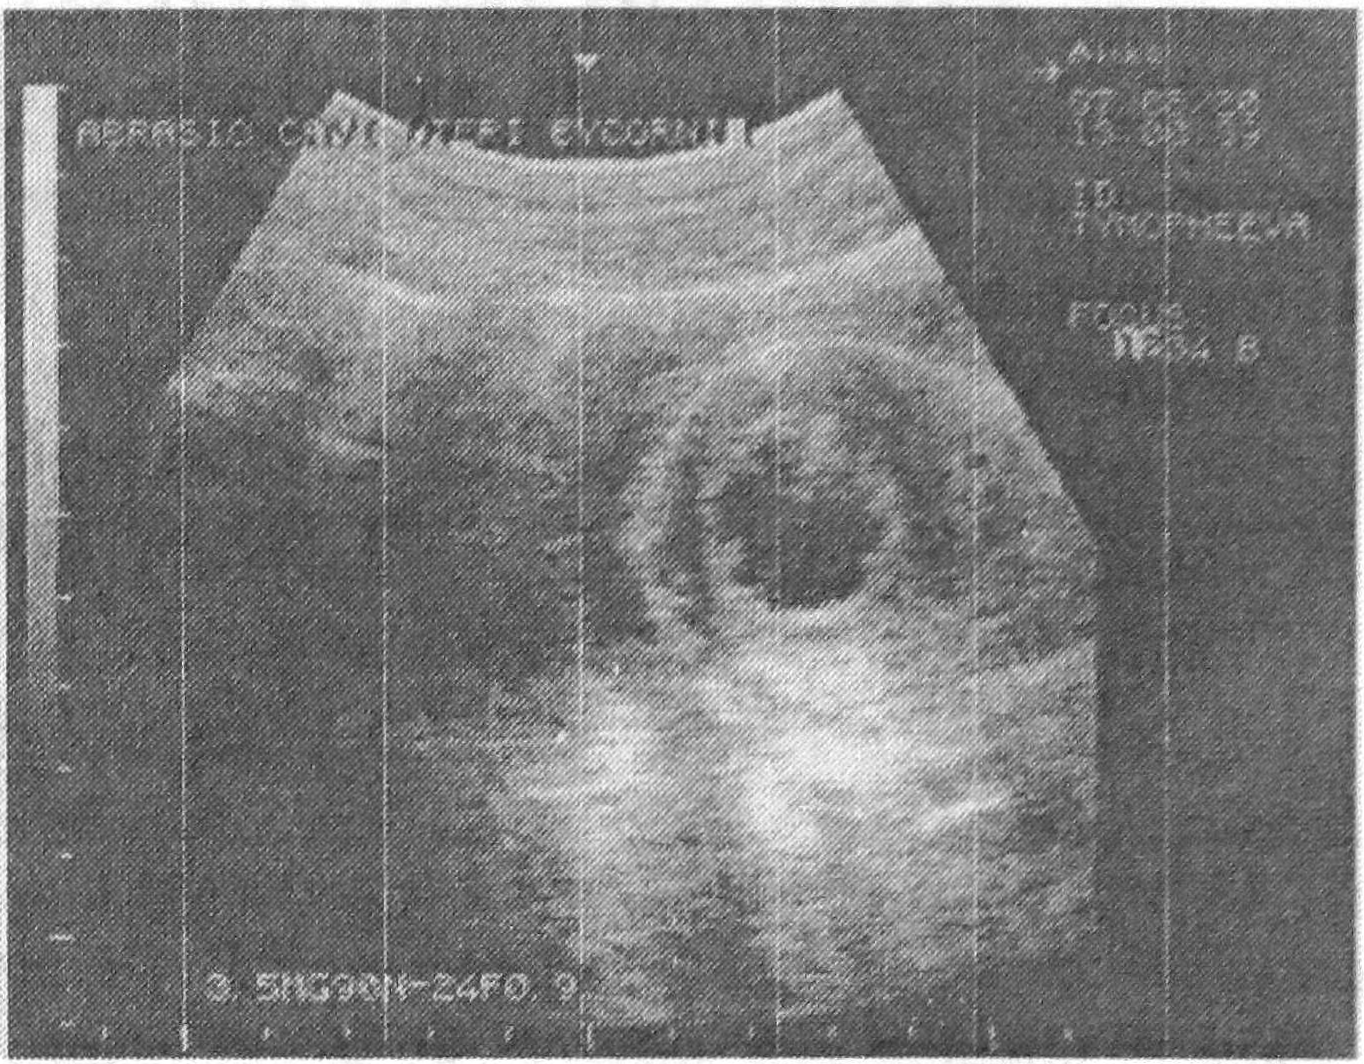

В настоящем наблюдении совершена переоценка значимости УЗИ в диагностике беременности, повлекшая за собой ряд неправильных действий. Однако еще на этапе первого гистологического исследования (при отсутствии частей плодного яйца и наличии ранней стадии секреции эндометрия) можно было заподозрить фибромиому. По-видимому, молодой возраст женщины (27 лет), отсутствие типичных жалоб (меноррагия), факт насильственного коитуса в анамнезе, задержка менструации стрессового характера склоняли клинициста к мысли о беременности в атретичном роге. И только в результате лапаротомии был поставлен правильный диагноз. Некротический детрит в полости узла (см. рис.) напоминал неразвивающееся плодное яйцо.

Рис. 1.